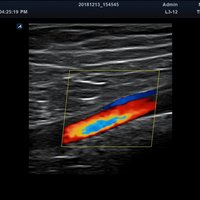

Anwendungsbereiche Abdomen MSK, Nerven, Karotis, periphere Gefäße, Schilddrüse, Mamma

Bildgebungs-Modi B-Modus, CF, M, PW, PD B-Modus, CF, M, PW, PD

• Farbdoppler: farbige Darstellung der Richtung des Blutflusses